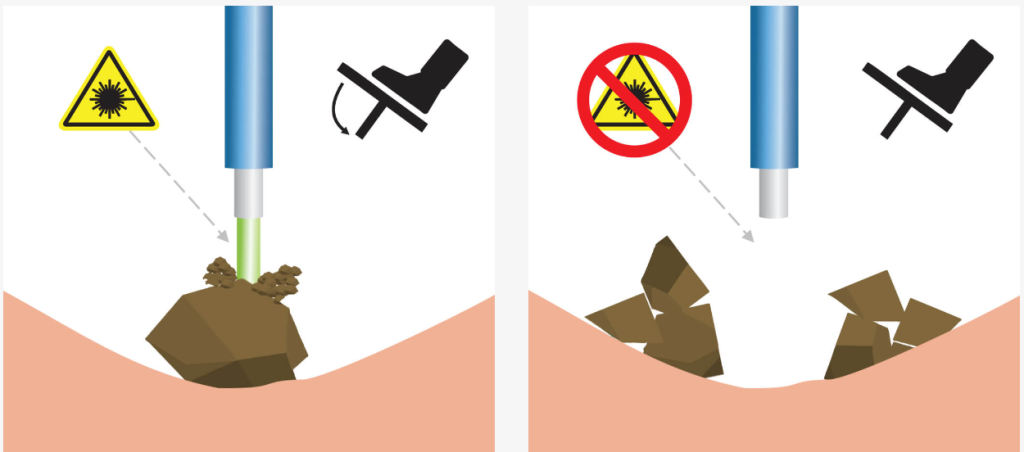

Функция "Детектор ткани"

"Детектор ткани" - это инновационная разработка, направленная на абсолютную максимизацию безопасности во время дробления камней. Технология особенно полезна при эндоскопическом лечении мочекаменной болезни.

Благодаря технологии детектирования тканей лазер различает какая ткань (твердая или мягкая) находится перед торцом хирургического волокна. Таким образом, при проведении литотрипсии, лазер автоматически останавливает подачу излучения при наведении на слизистую, тем самым повышая безопасность операции.

Технология позволяет уменьшить риск попадания лазерного излучения на окружающие мягкие ткани во время дробления камней и снизить нагрев окружающей жидкости вследствие “непродуктивных” импульсов, не достигших цели.

Демонстрация работы технологии

-

Перкутанная нефролитотрипсия.

-

Волокно 550 нм. Плотность = 1640 HU. Параметры: 3 Дж x 13 Гц = 39 Вт

-

Педаль нажата постоянно. Зеленый сигнал демонстрирует наличие излучения. Красный сигнал - его отсутствие.

Датчик ткани — это инновационная разработка «ИРЭ-Полюс», направленная на абсолютную максимизацию безопасности во время дробления камней. Данная технология призвана усилить развивающийся тренд на эндоскопическое лечение мочекаменной болезни.Принцип работы Tissue sensor заключается в том, что лазер различает какая ткань (твердая или мягкая) находится перед торцом хирургического волокна. Таким образом, при проведении литотрипсии, лазер автоматически останавливает подачу излучения при наведении на слизистую, исключая риск повреждения.

Tissue sensor позволяет достичь высокого уровня безопасности эндоскопического лечения мочекаменной болезни, снижается травматизация тканей во время литотрипсии.

Настройка чувствительности имеет несколько уровней. Это позволяет получить максимально корректное распознавание камней и мягких тканей даже в сложных условиях, например, при плохой видимости, плохом оттоке ирригационной жидкости, повышенной «пыльности» камня, при фрагментации в режиме «попкорнинга» или если дробление с прямым контактом камня и волокна невозможно.

В лазере UROLASE MAX функция «Детектор ткани» установлена и доступна к работе сразу после ввода лазера в эксплуатацию.